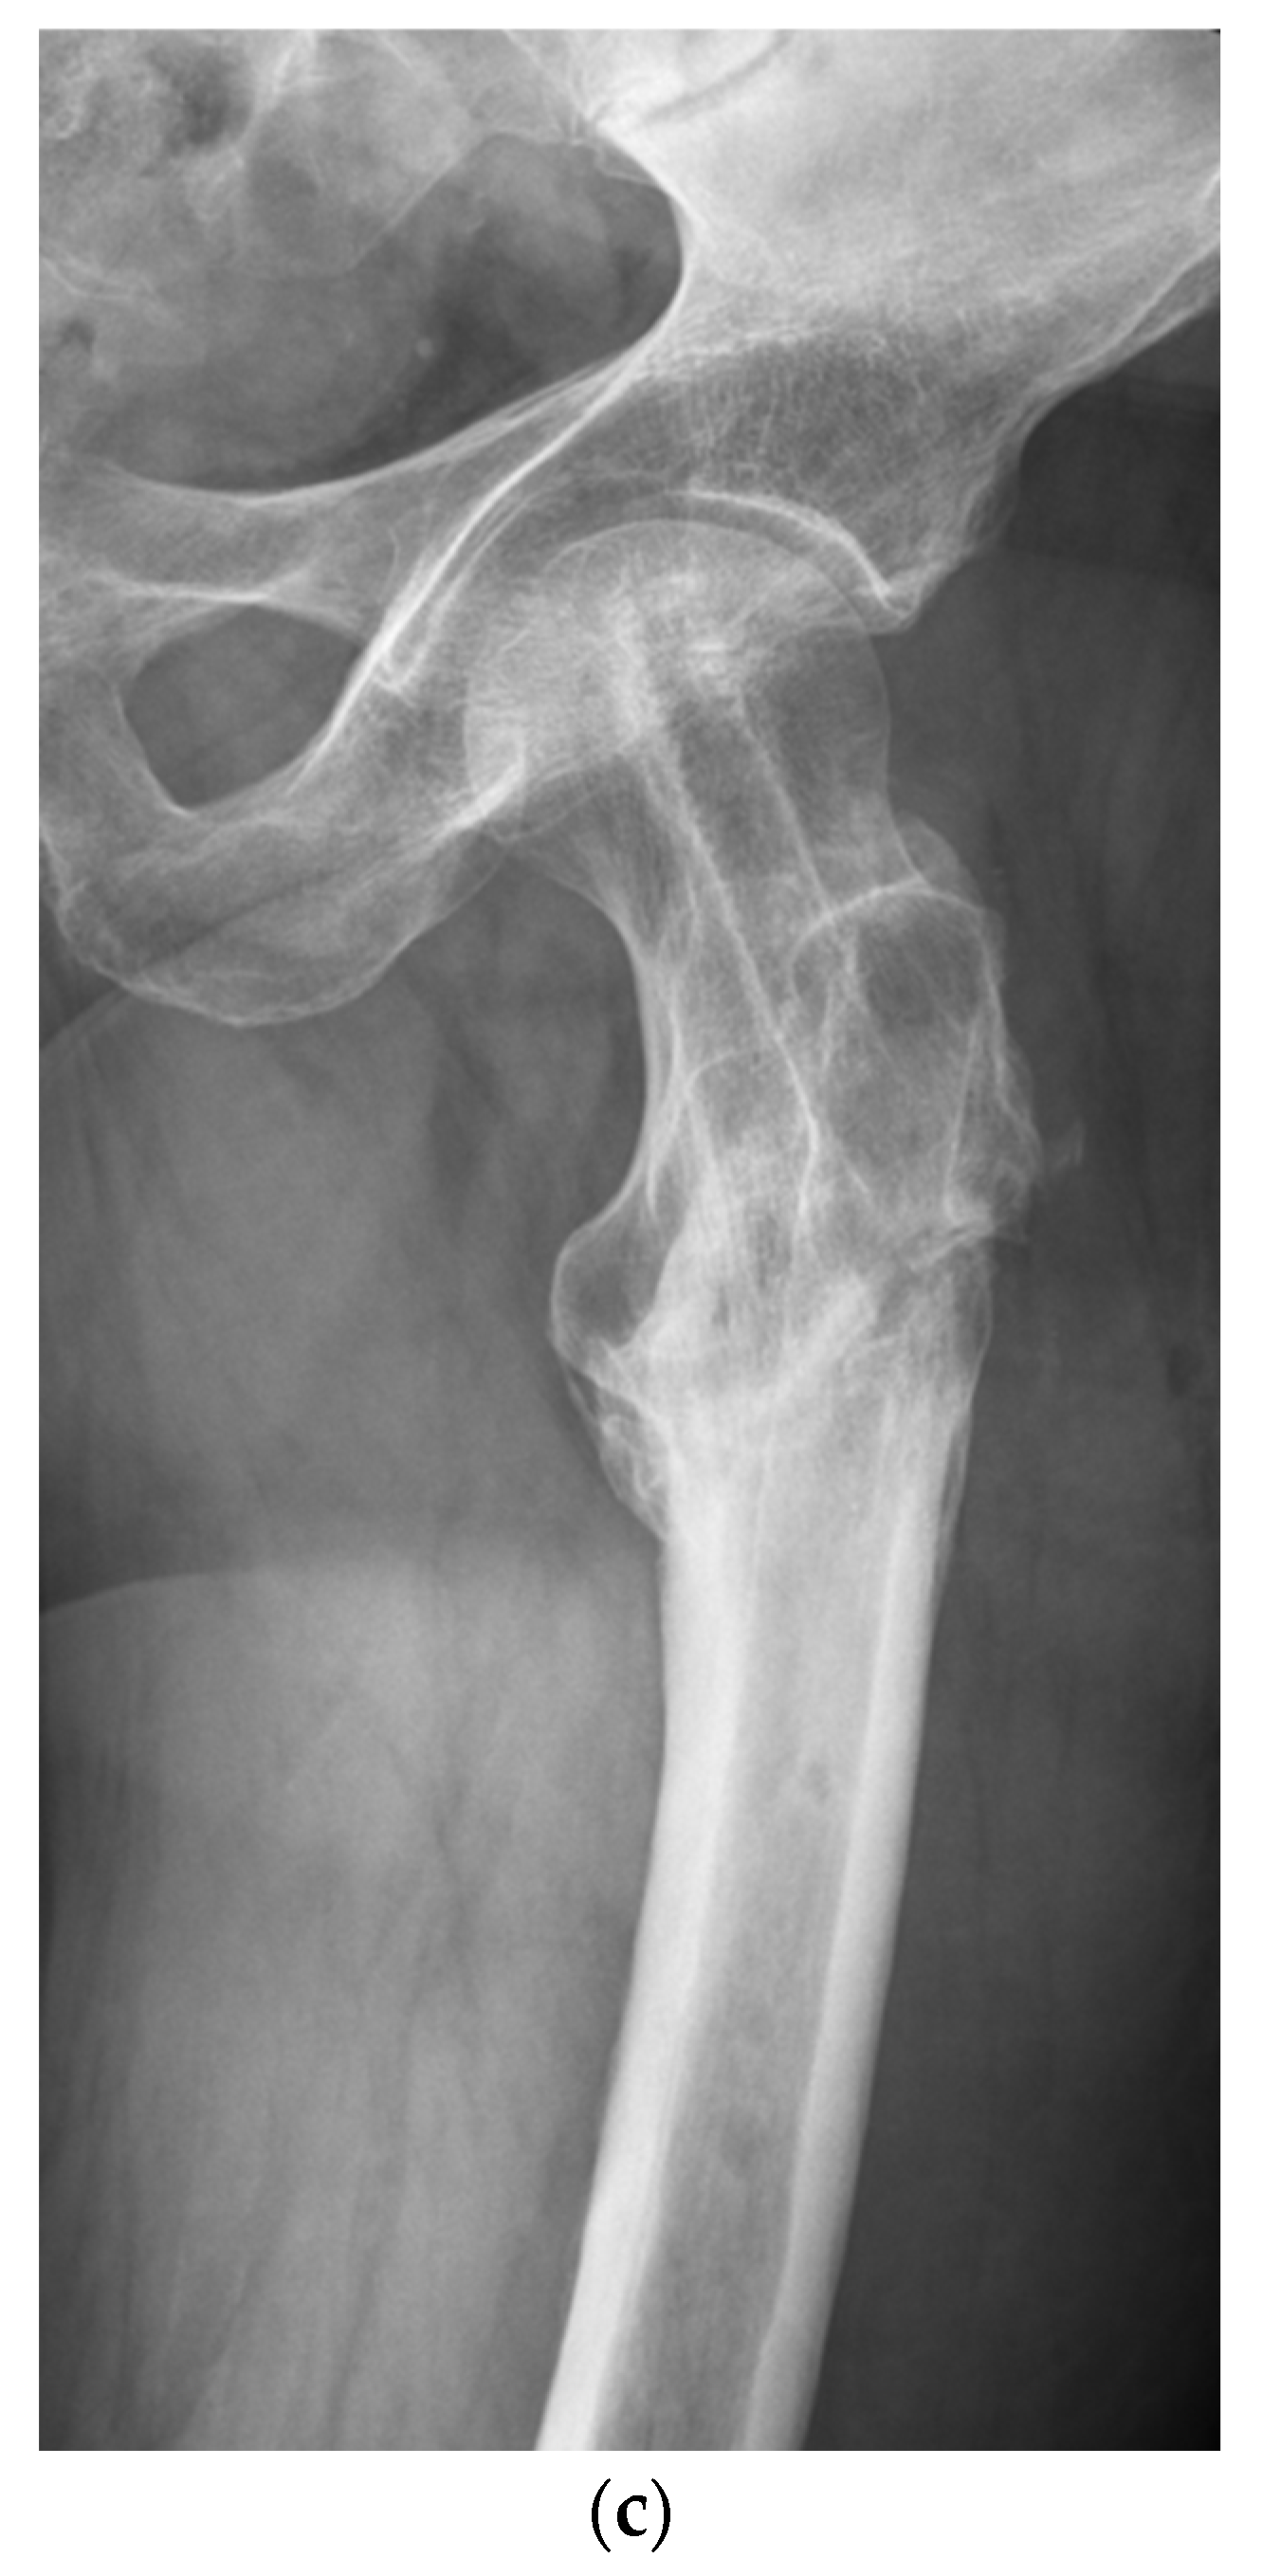

A retrospective analysis of the in-house databases of two European level I trauma centers was carried out for consecutive patients from January 2010 to March 2020. A total of 68 consecutive patients (21 women and 47 men) with the diagnosis of aseptic nonunion following AO/OTA 31 A1, 31 A2, 31 A3, very proximal 32 A13, 32 B13 and 32 C13 fractures were included (Figure 1; p < 0.0001). Patients aged 18 years and older who had undergone surgical revision for trochanteric and subtrochanteric nonunion with revision cephalomedullary nailing (Gamma3®, Stryker Corp., Kalamazoo, MI, USA; Trigen™ Intertan™, Smith & Nephew Inc.; Memphis, TN, USA; Figure 2a–c) and 95-degree angled blade plating (DePuy Synthes GmbH, Oberdorf, Switzerland; Figure 3a–c) were included. Pathologic fractures, fractures treated by total hip arthroplasty (THA) and periprosthetic fractures or extramedullary fixation devices were excluded from the study a priori, as were patients younger than 18 years and patients unable to give consent. The inclusion and exclusion criteria were strictly controlled and respected.

Figure 3. (a) Aseptic nonunion 6 months following cephalomedullary nail fixation in a reversed multi-fragmentary trochanteric fracture in a 48-year-old male patient. (b) Osseous healing three months after revision surgery using a 95-degree blade plate. (c) Situation after metal removal 12 months after surgical revision.